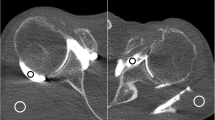

Attenuation (in HU) of the different anatomical structures did not vary significantly between the in vivo FPCT 5-s and 20-s acquisitions (all p ≥ 0.05). However, as expected, noise levels measured in the in vivo FPCT 5-s acquisitions were significantly higher compared to the FPCT 20-s acquisitions (all p < 0.05; Supplemental Table 2, Fig. 2).

Twenty-three-year-old male patient with flat panel CT (FPCT) 5-s (a-c) and thirty-year-old female patient with FPCT 20-s arthrography of the left shoulder joint (d-f): note significantly higher image noise (arrowheads) in FPCT 5 s (a) compared to FPCT 20 s (d), however with diagnostic image quality in both acquisitions. Arrows indicate intact glenoid labrum (a and d), humeral cartilage (b and e) and biceps tendon (c and e) in respective acquisitions with sharper contours in FPCT 20-s images

CNR values of the different joint compartments differed significantly between the in vivo FPCT 5-s and 20-s acquisitions with the latter providing a higher CNR in all compartments (all p ≤ 0.05; Supplemental Table 2, Fig. 2).

Technical quality of the intra-articular contrast material injection procedure was generally considered as perfect with no significant differences between the FPCT 5-s and 20-s acquisitions (p > 0.05). Subjective image quality of FPCT 20-s acquisitions was rated higher than FPCT 5-s acquisitions (median rating 1 in FPCT 20-s vs. 2 in FPCT 5-s acquisitions), however without reaching statistical significance (p > 0.05) (Supplemental Table 3, Fig. 2). Incidences of pathological findings, i.e. findings rated as 2 or 3 on the 3-point Likert scale according to the MR reference standard in the respective FPCT groups (5-s /20-s) were 5/4 (15 %/12 %) for cartilage, 7/16 (21 %/47 %) for bone, 10/16 (20 %/31 %) for labrum or biceps tendon, 5/11 (10 %/22 %) for rotator cuff and 9/4 (53 %/24 %) for AC-joint pathologies.

Differences between FPCT 5-s and 20-s acquisitions seen in the quantitative measures are moderately reflected in the qualitative ratings. A slight increase in sensitivity for labrum or biceps tendon pathology (40 % vs. 50 %) and a marked increase for cartilage and rotator cuff pathologies (40 % vs. 75 % and 20 % vs. 73 %, respectively) were noted for FPCT 20-s vs. 5-s acquisitions. Although the FPCT 20-s acquisitions delivered better image quality with fewer artifacts, the diagnostic performance for the remainder of joint pathologies with regard to specificity, PPV, NPV and accuracy was comparable to FPCT 5-s acquisition. This corroborates findings of recent studies with excellent image quality for bone visualization using cone-beam CT [26] and good diagnostic performance for cartilage lesions in FPCT using an 8-s intermediate radiation dose protocol [9]. In contrast to published studies on the performance of MDCT arthrography for cartilage and labrum defects of the shoulder [27–31], sensitivity of FPCT was low. Although generally higher in 20-s acquisitions sensitivities for both pathologies amounted to only 75 % and 50 %, well below reported values in MDCT arthrography. A major source for deterioration of image quality are different attenuation profiles and incomplete trajectories of the volume of interests of a 200 ° C-arm rotation around the shoulder joint which can lead to marked truncation artefacts. In addition, as seen in our FPCT arthrograms, potential high spatial resolution of FPCT can be hampered by susceptibility to cone-beam and ring artifacts, decreasing sensitivity for e.g. cartilage and labrum defects. MDCT arthrography of the shoulder is less affected by beam hardening artifacts, although photon starvation in analogy to FPCT is an issue [32]. Additional artifacts may occur when using cone-beam instead of fan-beam geometry [5, 6, 33]. Patients with metallic implants were therefore excluded from this study as this was beyond the scope of this study.